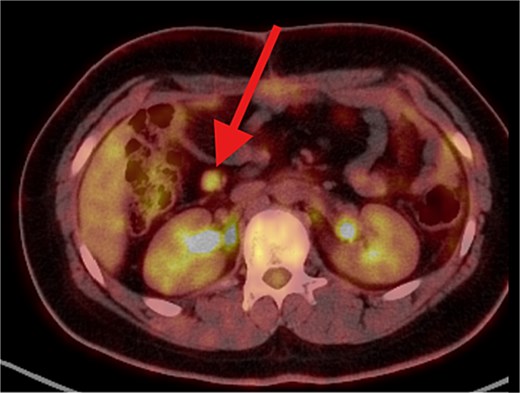

The patient underwent left lateral hepatectomy and cholecystectomy following diagnosis. Histopathology confirmed undifferentiated embryonal sarcoma (UES) of the liver with a 1 mm clear margin (Fig. 1); immunohistochemistry supported the diagnosis. The gallbladder showed chronic cholecystitis, and the lymph nodes were tumor-free. Postoperative imaging after two months revealed a recurrent mass near the stomach (Fig. 2), confirmed as recurrent UES by biopsy. Re-excision showed extensive necrosis and peritoneal infiltration. Positron emission tomography – computed tomography (PET-CT) later identified peritoneal and mesenteric metastases (Fig. 3). Follow-up PET-CT also revealed multiple small hypermetabolic hepatic nodules in addition to peritoneal and mesenteric lesions, indicating intrahepatic disease recurrence. Six cycles of chemotherapy resulted in near-complete resolution of metabolic lesions, with minimal residual activity. Follow-up imaging showed near-complete resolution of hepatic nodules, with only one residual, non-suspicious tiny nodule. After additional chemotherapy and targeted therapy cycles, PET-CT revealed new focal hypermetabolic activity near the splenic flexure, anterior to the spleen, raising concern for recurrence (Fig. 4). The patient underwent omentectomy and splenectomy. Histopathology confirmed metastatic UES in a 2.5 cm splenic lesion with hemorrhage and necrosis, and a 0.4 cm omental nodule, both completely excised. A total of 15 chemotherapy cycles were completed. Post-treatment imaging showed a mixed-density lesion in the splenic bed with FDG uptake, possibly post-surgical, and a new hypermetabolic mesenteric nodule (Fig. 5). Magnetic resonance imaging showed a cystic post-surgical collection without enhancing lesions. Subsequent imaging revealed regression of the splenic bed lesion and resolution of the mesenteric nodule; however, a new hypermetabolic mesenteric density emerged (Fig. 6). The lesion was placed under active surveillance, with additional chemotherapy administered and repeat imaging scheduled to assess response. Bilateral axillary lymph nodes showed reactive hypermetabolism. The patient, having undergone hepatectomy, splenectomy, and multimodal therapy, remains under close surveillance with encouraging treatment response.

PET/CT scan showing a clear surgical bed. There is heterogeneous mostly cystic lesion at splenic surgical bed with moderate FDG uptake at its peripheral soft tissue component, mostly post-surgical sequel. Interval development of right abdominal para median soft tissue / mesenteric nodule with moderate hypermetabolic activity. Suspicious for metastatic process.